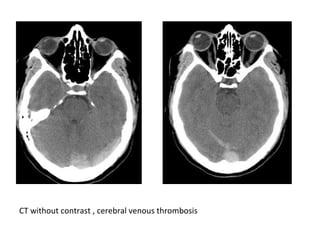

CT without contrast , cerebral venous thrombosis

CT without contrast , cerebral venous sinus thrombosis